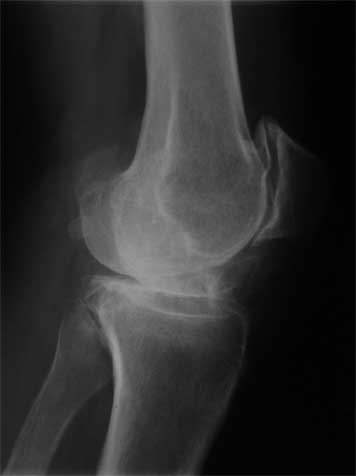

Уважаемые коллеги, пациентка 45 лет около 9 мес назад была прооперирована по поводу правостороннего коксартроза э/п LCS Complete RP.

послеоперационный период без особенностей, объем движений в 6 мес с/р - 110/0/0. Через 9 мес после операции возник напряженный гемартроз (без травмы, перегрузок), получено до 190 мл свежей крови, далее фиксация в ортезе, повторные пункции. через 2 нед выписана из стационара без признаков гемартроза. Через 2 нед аналогичная ситуация. Вопросы :причина? как лечить?